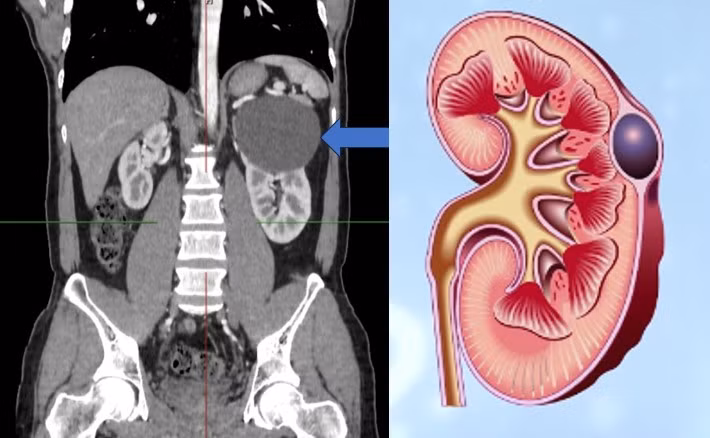

![]() |

| Hình ảnh nang đơn thận - Ảnh BSCC |

Để chẩn đoán nang đơn thận, hầu hết các trường hợp nang đơn thận được chẩn đoán tình cờ khi thăm dò chẩn đoán hình ảnh như siêu âm, chụp cắt lớp vi tính, …Vấn đề cần chú ý trong chẩn đoán nang đơn thận là cần phân biệt với nang thận trong bệnh thận đa nang, ung thư thận, nang thận ung thư hóa.